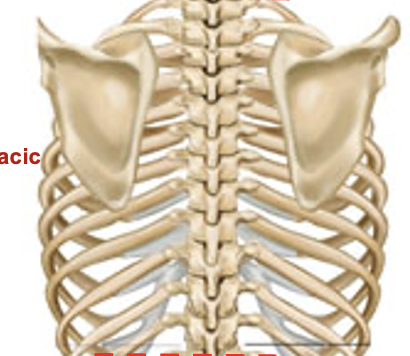

thoracic

12 bones that make up this segment of the vertebral column

dorsal column/funiculus

white matter located in between dorsal horns; contain multiple tracts

ventral column/funiculus

white matter located between two ventral horns; contain multiple tracts

lateral funiculus

between lateral edge of dorsal and ventral horns; contains multple tracts